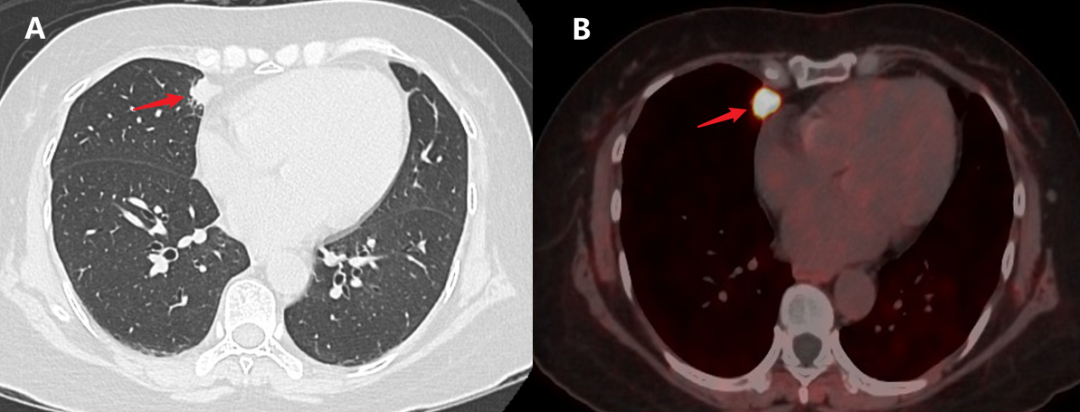

▲图A:CT平扫肺窗发现右肺中叶内侧段胸膜下小结节;图B:PET/CT发现右肺中叶内侧段结节代谢明显增高,提示肿瘤细胞处于明显增殖状态。

一次偶然,王伯得知茂名市人民医院近年引进了一台先进的检查设备PET/CT,在肿瘤检查方面具有突出优势,能够抓到0.5厘米以上的微小肿瘤。王伯立刻联系茂名市人民医院核医学科,该科梁汉祥副主任经过对比分析王伯3年来的体检资料,发现王伯的情况符合核医学科的科研项目入组条件,还可以获得一定比例的费用补助,王伯马上决定行全身PET/CT扫描,结果提示:右肺中叶内侧段早期肺癌。

尽管最后确诊了肺癌,但是王伯勇敢面对,在茂名市人民医院胸外科接受了微创手术,病理提示:原位腺癌,只需手术切除,无需放化疗。王伯表示:“幸好做了PET/CT,早点查出来早点解决,我也不用总是提心吊胆了。”王伯放下了心头大石,又恢复了对生活的热情。

核医学科李繁主任表示,早期肺癌通常无任何临床症状,体积增长比较慢,经常会错过最好治疗时机,PET/CT是临床上可以早期准确评估肿瘤代谢状态的设备。